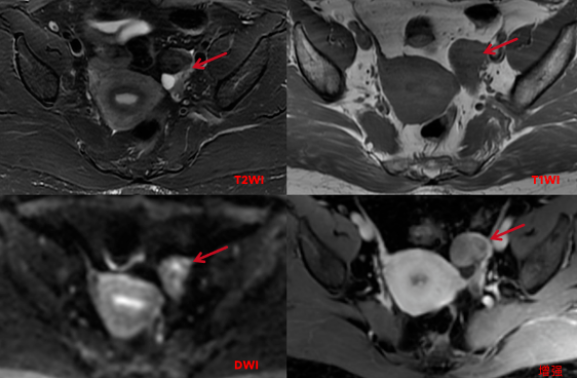

盆腔MRI平扫及增强:左侧附件区可见稍长T1短及稍短T2信号,大小约25x30x30mm,T2WI压脂像呈稍低信号,边界清楚,边缘较光滑,DWI呈周边不均匀稍高信号,中心信号稍低, 增强扫描不均匀中等强化,其后方另见多个小囊状长T2信号,增强扫描病变囊壁稍厚,光滑,轻微强化。

影像诊断:左侧附件区囊实性占位,倾向良性可能性大,Brenner瘤或卵泡膜纤维瘤可能性大,建议临床活检。